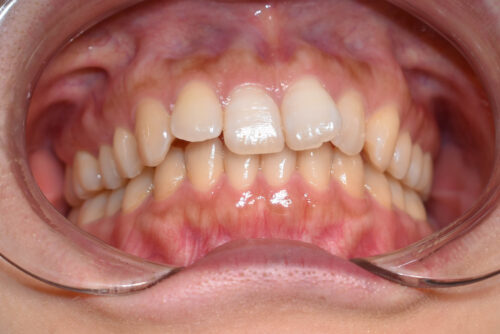

初診時年齢 27歳 女性

歯のでこぼこ(叢生)

と

過蓋咬合

を主訴に

右側が アングル2級とよばれる

出っ歯傾向の状態で

上の正中が

半歯分 ずれている状態でした。

また 下あごの 歯が見えず

過蓋咬合を呈していました。